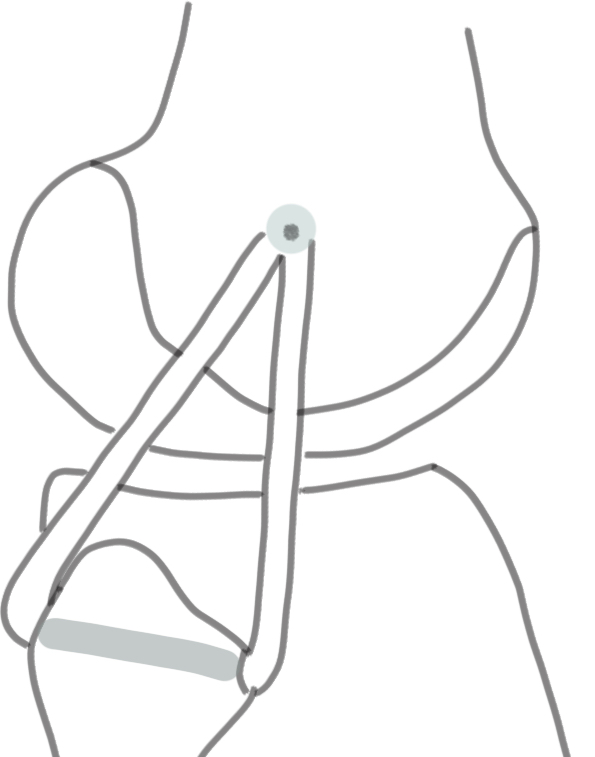

LaPrade surgical technique PLC PDF

LaPrade surgical technique ACL / PCL / PLC PDF

Xray following PCL reconstruction, LCL and politeus reconstruction. CT demonsrating popliteus and LCL tunnels